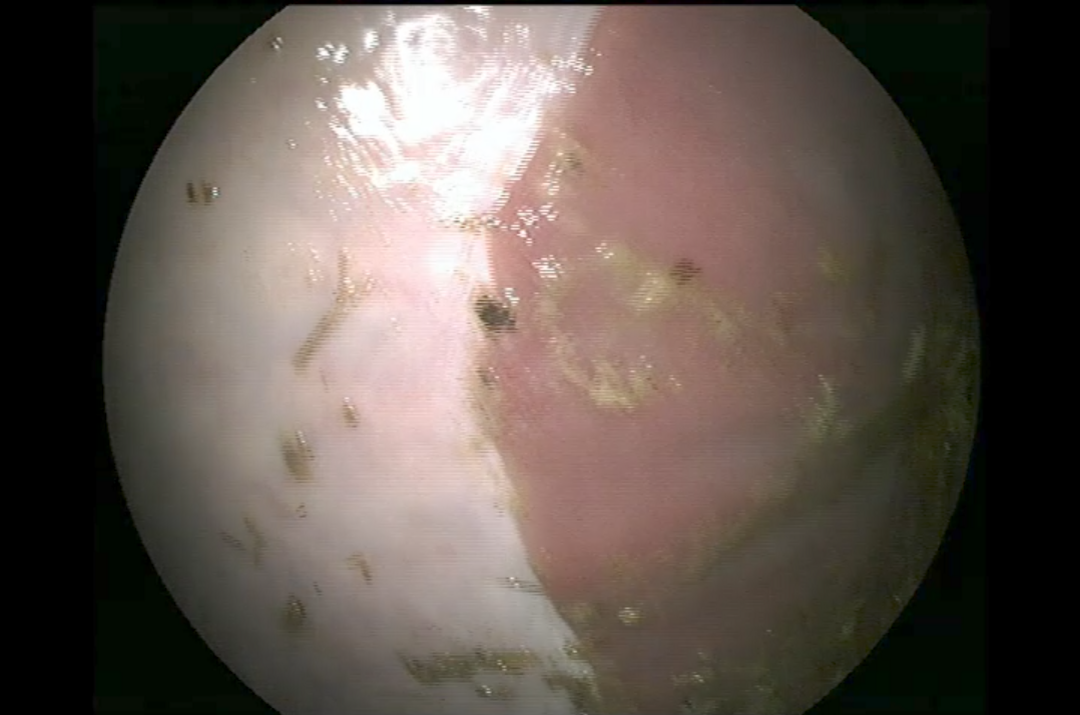

| • | Um den Stress bei der Gastroskopie zu minimieren und das Einbringen des Gastroskops zu erleichtern ist eine leichte Sedierung für die Untersuchung notwendig. Nach der Sedierung wird ein langer, flexibler Schlauch, der eine Optik trägt, durch die Nüster des Pferdes eingeführt und vorsichtig durch die Speiseröhre in den Magen vorgeschoben. Dabei werden Speiseröhre und Magen beurteilt. Nur bei einem nahezu vollständig leeren Magen ist eine genaue Untersuchung der Magenwände, der Schleimhaut und des Magenein- und ausgangs möglich. |

Besondere Aufmerksamkeit gilt auffälligen Bereichen, wie Rötungen, Blutungen oder Geschwüren. Es können darüber hinaus auch andere Probleme wie Magenentleerungsstörungen oder Parasitenbefall (z. B. Magendasseln) diagnostiziert werden. Falls notwendig, können während der Gastroskopie Proben entnommen und Fotos und Videos zur weiteren Auswertung angefertigt werden.